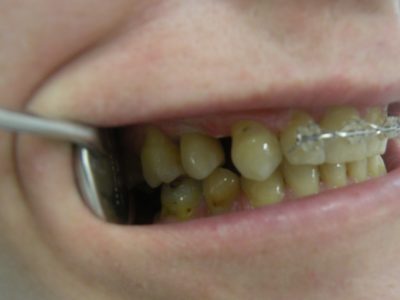

Interdisciplinarietà

Si tratta di una collaborazione interdisciplinare di un team di vari specialisti in odontoiatria, con un unico scopo: il raggiungimento di risultati perfetti nella riabilitazione della cavità orale di ogni singolo paziente.